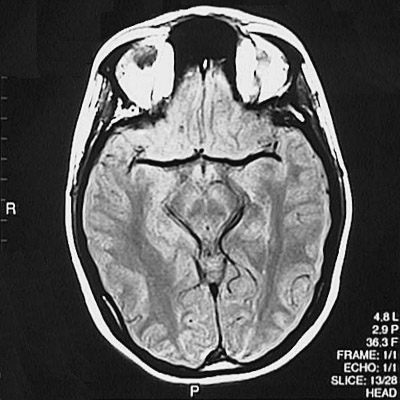

This is a normal axial proton density MRI scan demonstrating the inferior frontal lobe and temporal lobe and occipital lobe and cerebral peduncle and substantia nigra and red nucleus and aqueduct of Sylvius and frontal sinus and orbit.